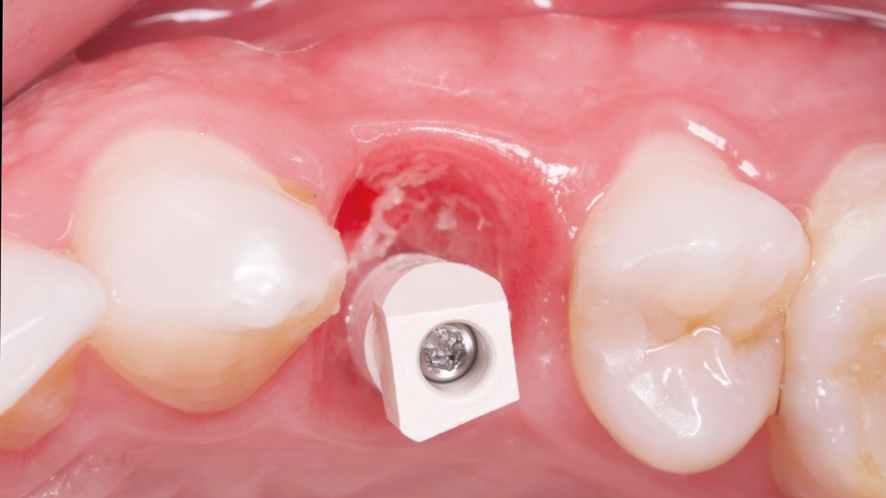

Visto todos os planejamentos realizados, buscou-se então dar ínicio ao procedimento cirúrgico. A exodontia foi realizada de forma minimamente invasiva, utilizado periótomos (Supremo) fazendo movimentos de lateralidade, buscando descolar as fibras periodontais do dente, visando assim conservar ao máximo os tecidos gengivais adjacentes após essa etapa, até sua avulsão.

Após a exodontia foi posicionado o guia cirúrgico impresso e iniciou-se o protocolo de fresagem do kit cirúrgico Implaguide da Implacil De Bortoli: fresa lança 2,0, seguida pela fresa 3,5×13, buscando subfresagem para maior estabilidade primária. O implante dentário instalado foi o Maestro de 4x13mm (Implacil De Bortoli). Foi realizado em seguida a instalação do pilar Ideale 4,5 x 4 x 2,5 mm e a coifa parafusada do pilar Ideale 4,5x4mm.

O GAP vestibular foi preenchido com enxerto ósseo heterógeno com matriz colágeno Extra Graft (Implacil De Bortoli), o qual foi colocado e compactado.

Em seguida foi realizado a captura do provisório em PMMA na coifa de titânio com resina fluida e após acréscimos, acabamento e polimento fora da boca, o provisório foi aparafusado e a cirurgia foi finalizada sem a necessidade de sutura.